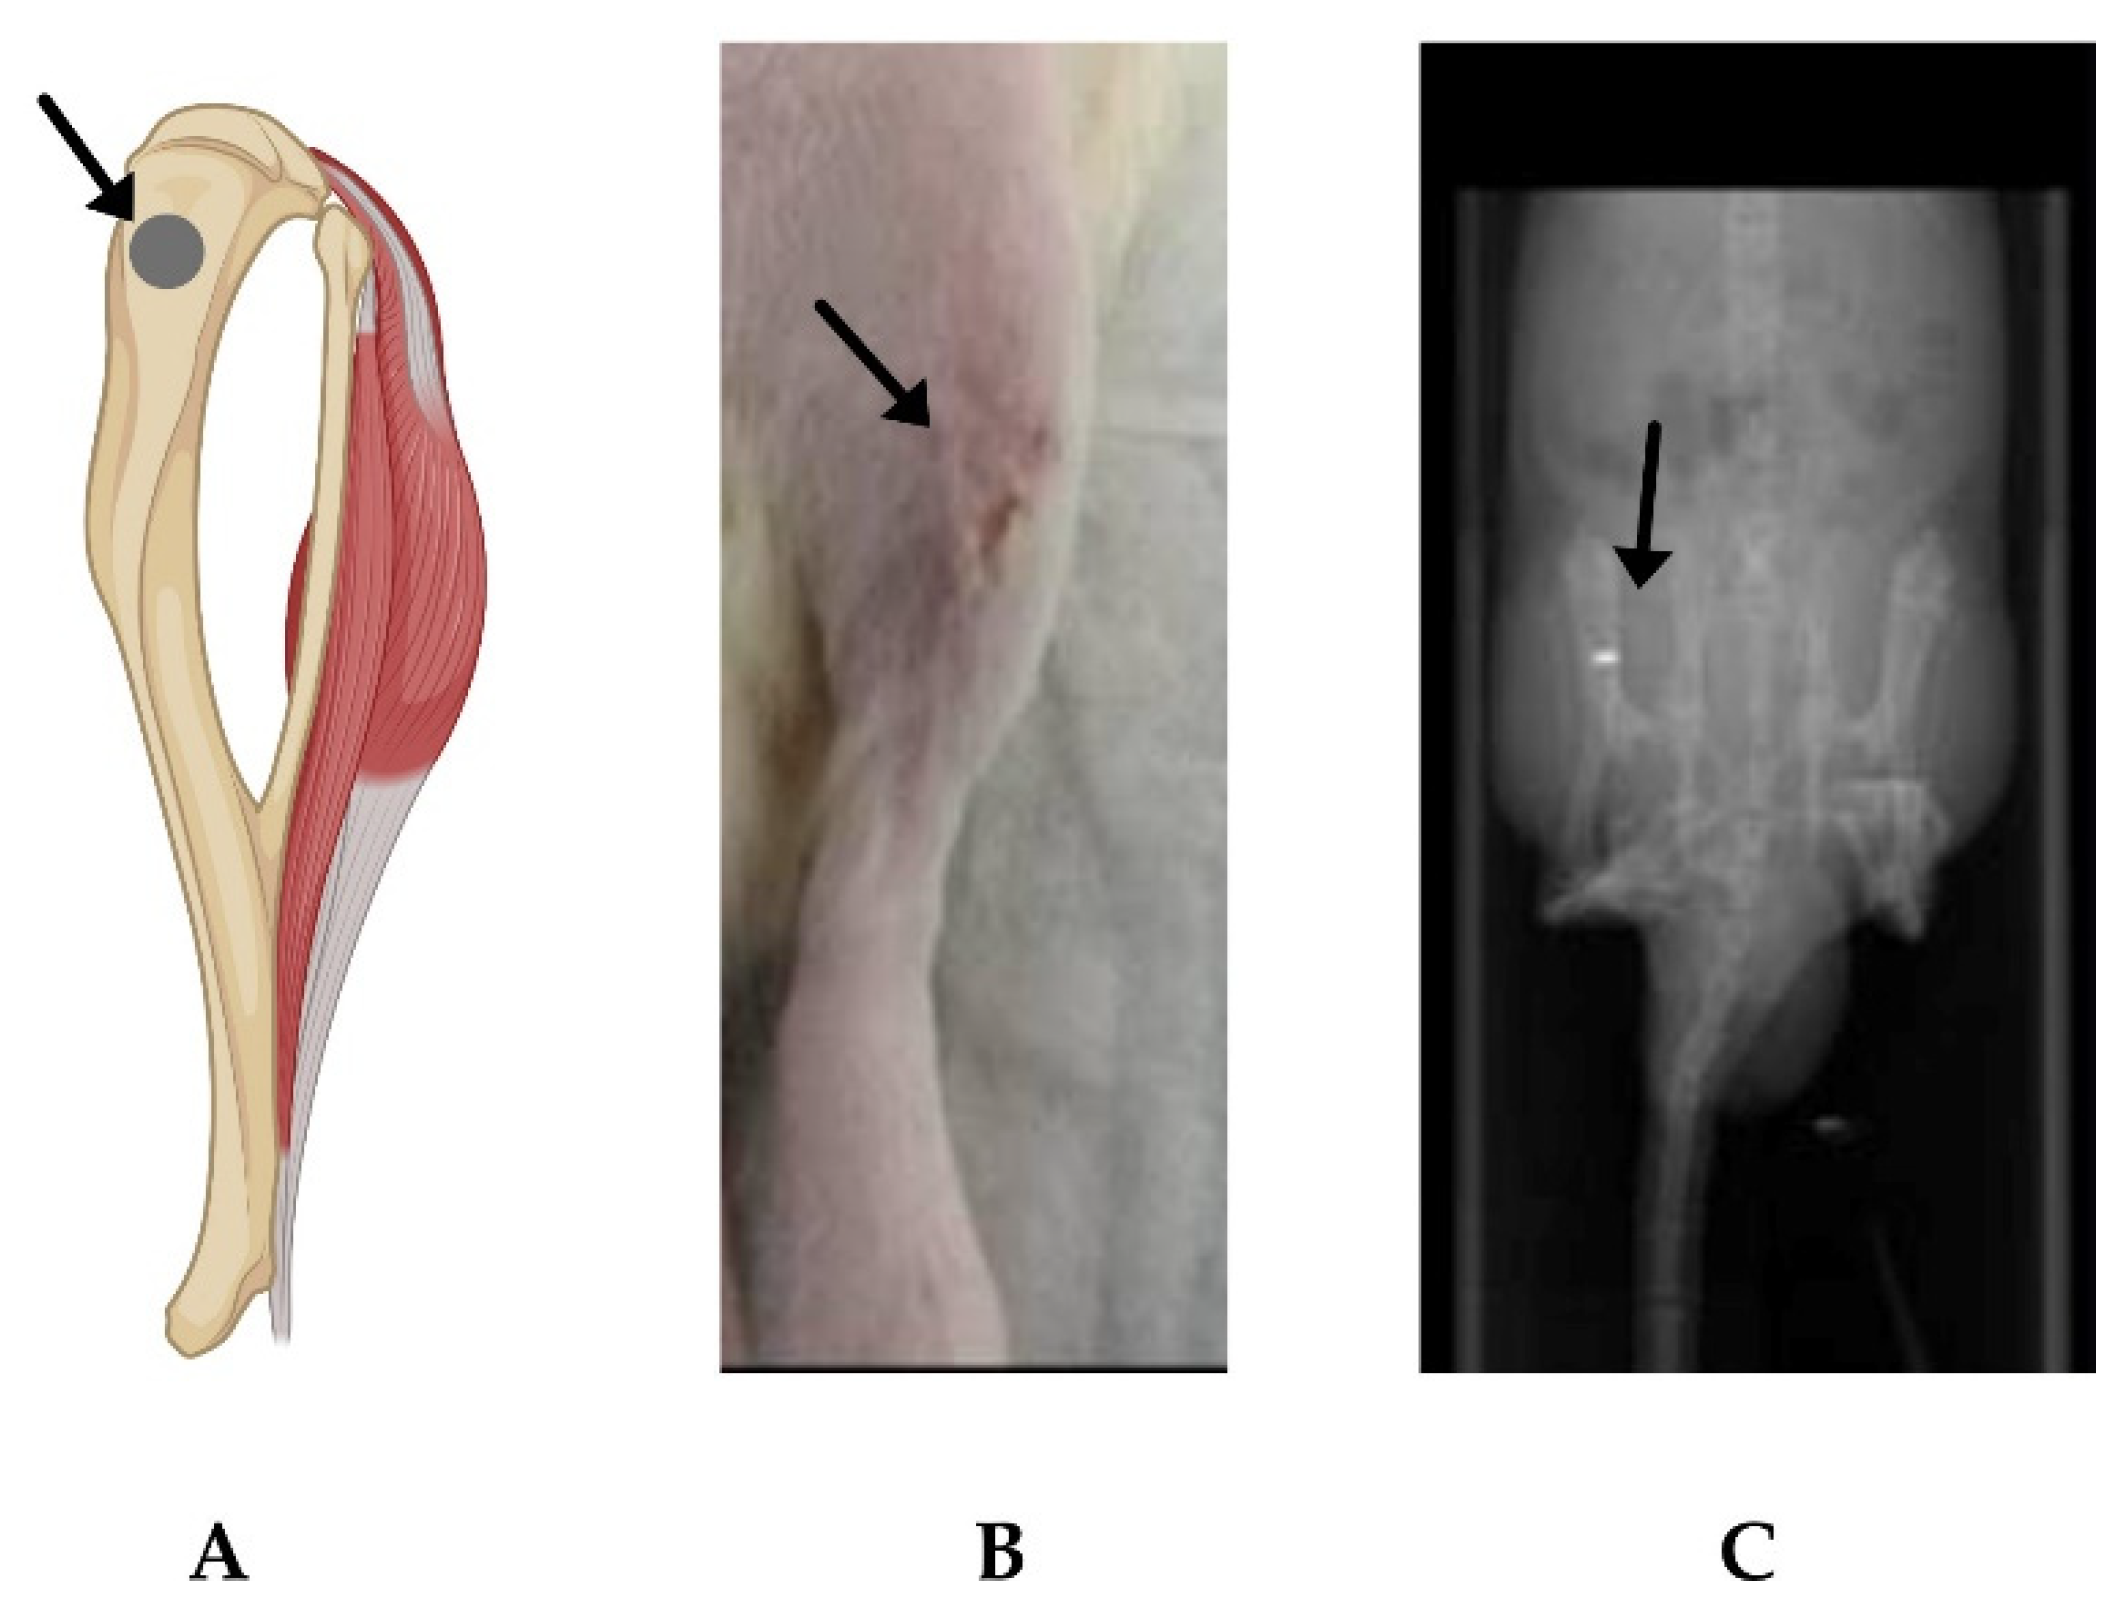

2.2. In Vivo Evaluation of α-MSH-SM-Liposomes

4.6. Imaging of α-MSH-SM-Liposomes